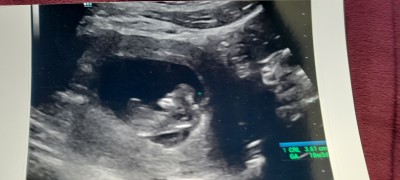

Kizlar ultrasonuma bakar misiniz??

cinsiyetten anlayanlar yorumlanabilir mi :))

10+3

Daha organi olusmamis tahmin yapilamaz ki

2 hafta daha bekle canim ancak 12. Haftada tahmin yaparlar oda nadir

Cinsiyeti tam 12 de oluşuyor 10 haftada doktorlar tahminde bulunamazken biz nasıl bilelim bir kaç hafta daha bekleyin

Özel hastaneler tahminde bulunuyorlar ama yanılma payi yüksek devlette 14 yada 15 haflatik olmaniz gerekiyor

Canım daha erken belli olmaz organı 12 haftada gelişmeye başlıyor

Yuvarlak kesesi var benimde böyle ve kız dedi :)